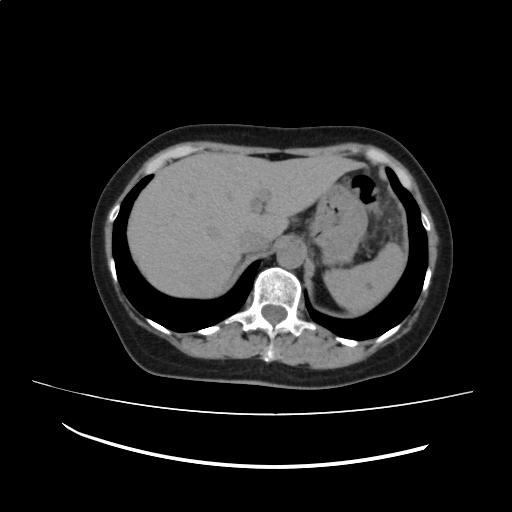

肝内に明らかな占拠性病変(SOL)を認めない。

膵体部に石灰化を認める。主膵管の拡張は認めない。

脾臓に小低吸収域(LDA)を認め、脾門部脂肪と考える。前回と比較して著変なし。

(Impression)

前回検査と比較して著変はない。

CT画像98

(96/198)